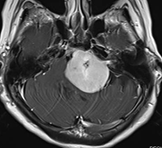

錐体斜台部髄膜腫

この部位は脳神経がすだれのように走行しており、腫瘍により脳幹・脳神経(外転神経・顔面神経・聴神経など)が圧迫されると物が2つに見えたり、耳が聞こえなくなったり、さらに腫瘍のサイズが大きくなると生命に危険な状態となります。

(術前MRI)

(術後MRI)

このように比較的大きい腫瘍が脳幹を圧迫している場合は、重篤な症状をきたし生命に危険が伴う可能性があるため、早急に手術が必要です。